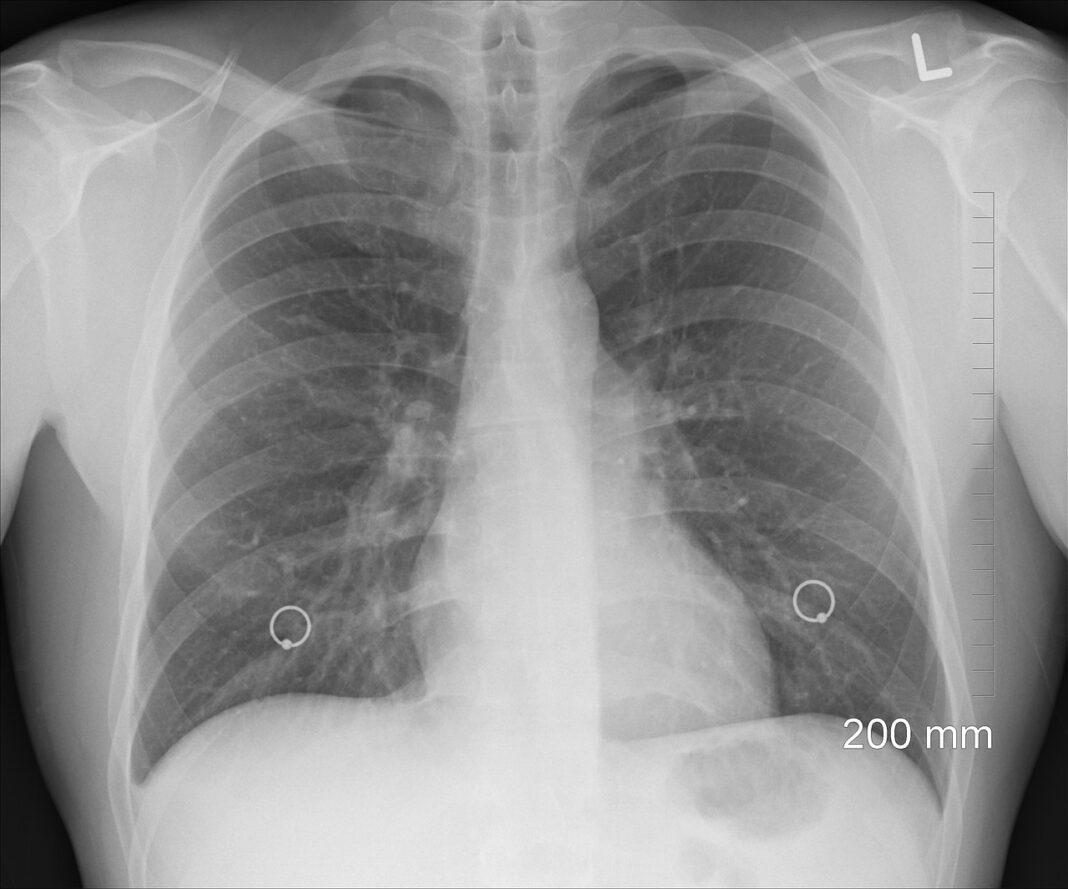

En esta línea, han trabajado en el desarrollo de un algoritmo mediante el uso de biomarcadores tumorales, con el fin de ofrecer una prueba diagnóstica económica, estandarizada, poco invasiva y accesible a cualquier laboratorio de cualquier hospital. El uso de este algoritmo ofrecería unos resultados de sensibilidad, especificidad y valores predictivos muy superiores a los obtenidos por otras pruebas. “Hemos evaluado los resultados de la aplicación de este panel de biomarcadores en diferentes hospitales y hemos realizado una validación externa de los resultados de la aplicación de este algoritmo con unos resultados muy positivos, mejores que los obtenidos por otras pruebas como las técnicas de imagen, entre otras”, subraya el Dr. Barco.

De esta forma, como asevera el Dr. Barco, el laboratorio podría participar aplicando este algoritmo de biomarcadores a los pacientes de riesgo (aquellos con historia clínica compatible con un posible cáncer de pulmón), “agilizando el posible diagnóstico y, ante un posible cribado, preseleccionando aquellos con un riesgo alto de cáncer, a los que se les realizarían las pruebas de imagen. Por lo tanto, se podría llegar a un número mayor de pacientes optimizando los recursos y ayudando a un cribado más eficiente”.